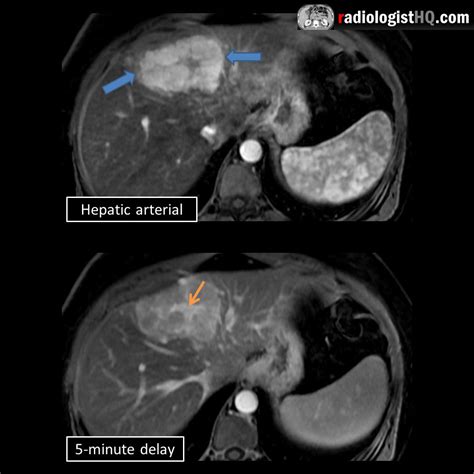

• Magnetic Resonance Imaging (MRI): MRI uses magnetic fields and radio waves to produce detailed images of the liver. It is often the preferred method for diagnosing FNH due to its high sensitivity and specificity.